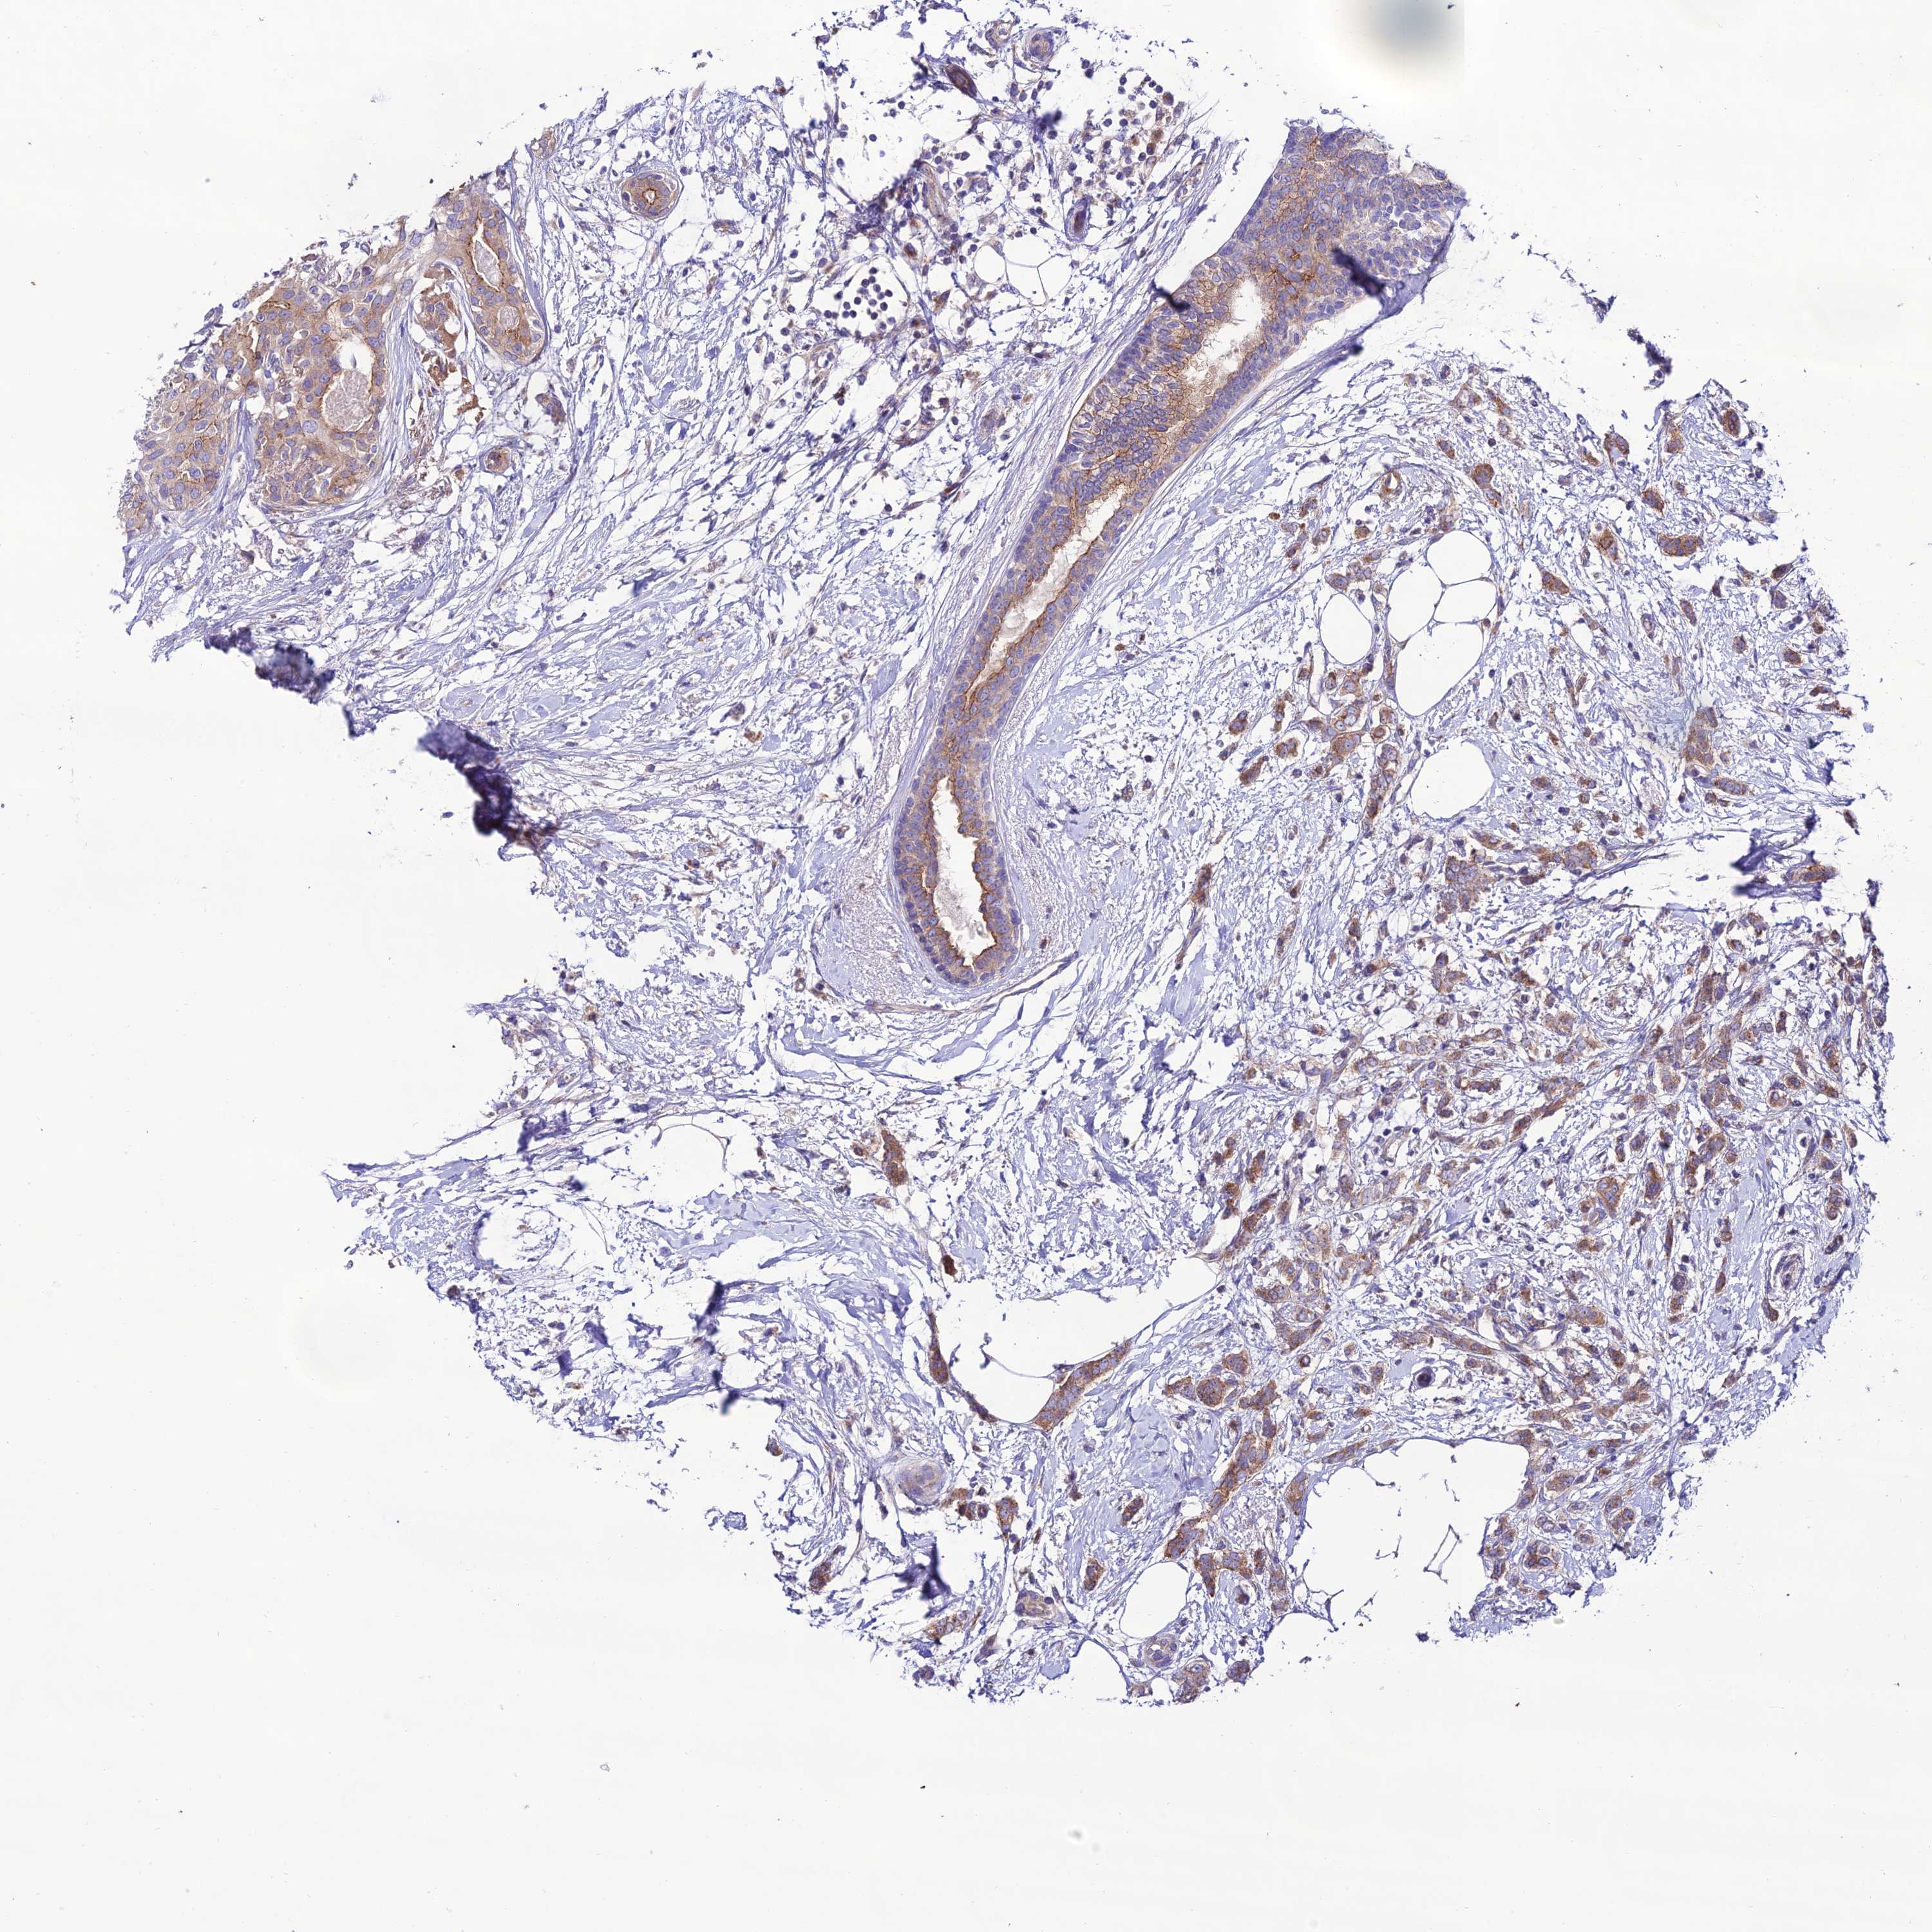

CANCER BREAST CANCER Show tissue menu

BRCA TCGA BRCA VALIDATION PROTEIN EXPRESSION

Breast cancer

Human cancer

Breast invasive carcinoma